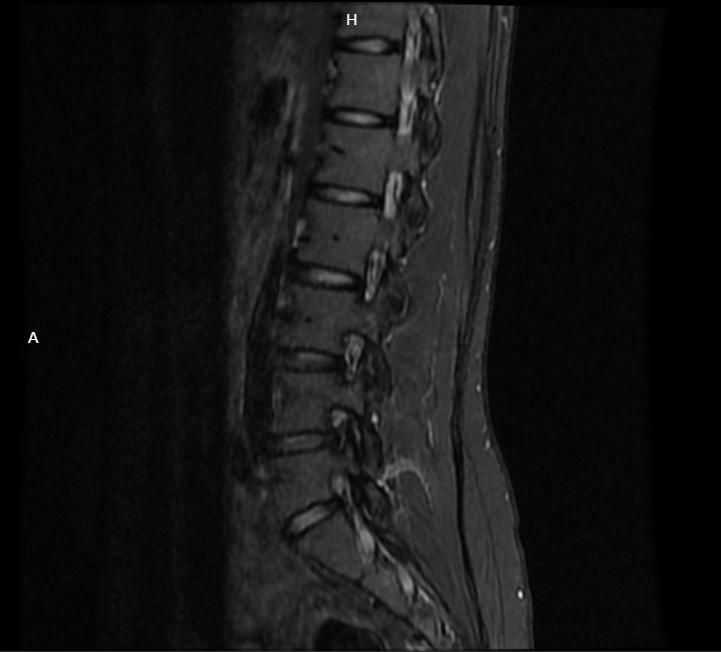

腰椎间盘突出下肢麻木、放射性疼,同时发凉,怎么回事?

临床中,当腰椎间盘突出的病人出现下肢麻木和发凉的感觉时,多因突出的椎间盘突出的髓核压迫刺激神经导致。

腰椎间盘突出的病人产生下肢放射性疼痛,主要是在腰椎间盘突出后,对神经根有化学刺激和物理压迫所引起的。

麻木,通常是由于神经受压较重,且受压时间较长,神经受损所导致的,并且应为受累的神经根位置不同,所表现的下肢具体症状部位也不同。

肢体的发冷发凉,是因为当突出的髓核刺激神经特别是下肢的交感神经时,会反射性引起下肢血管的收缩,导致下肢血流量的降低,病人会感觉下肢发凉。